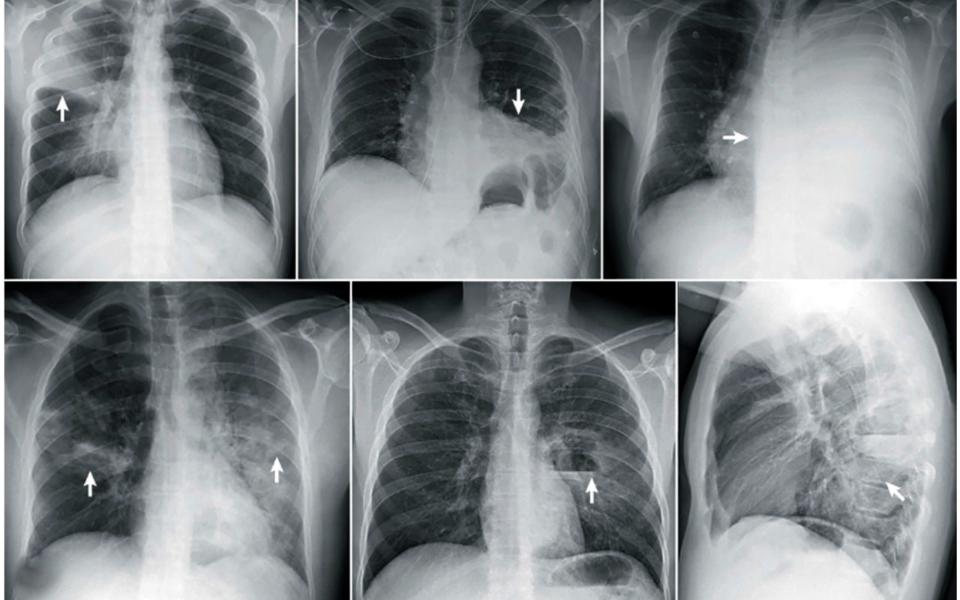

Пациентка пришла в 14-ю городскую поликлинику с жалобами на затруднённое дыхание. Терапевт заподозрил пневмонию: при аускультации стали слышны влажные мелкопузырчатые хрипы. Бригада скорой помощи направила пациентку в ОКБ. Там в ходе обследования лёгких выявили двустороннюю пневмонию средней степени тяжести. Лёгкие были поражены на 60%. Ситуацию осложняло и то, что у пациентки был диабет 2 типа.

Иллюстрации:  ОКБ